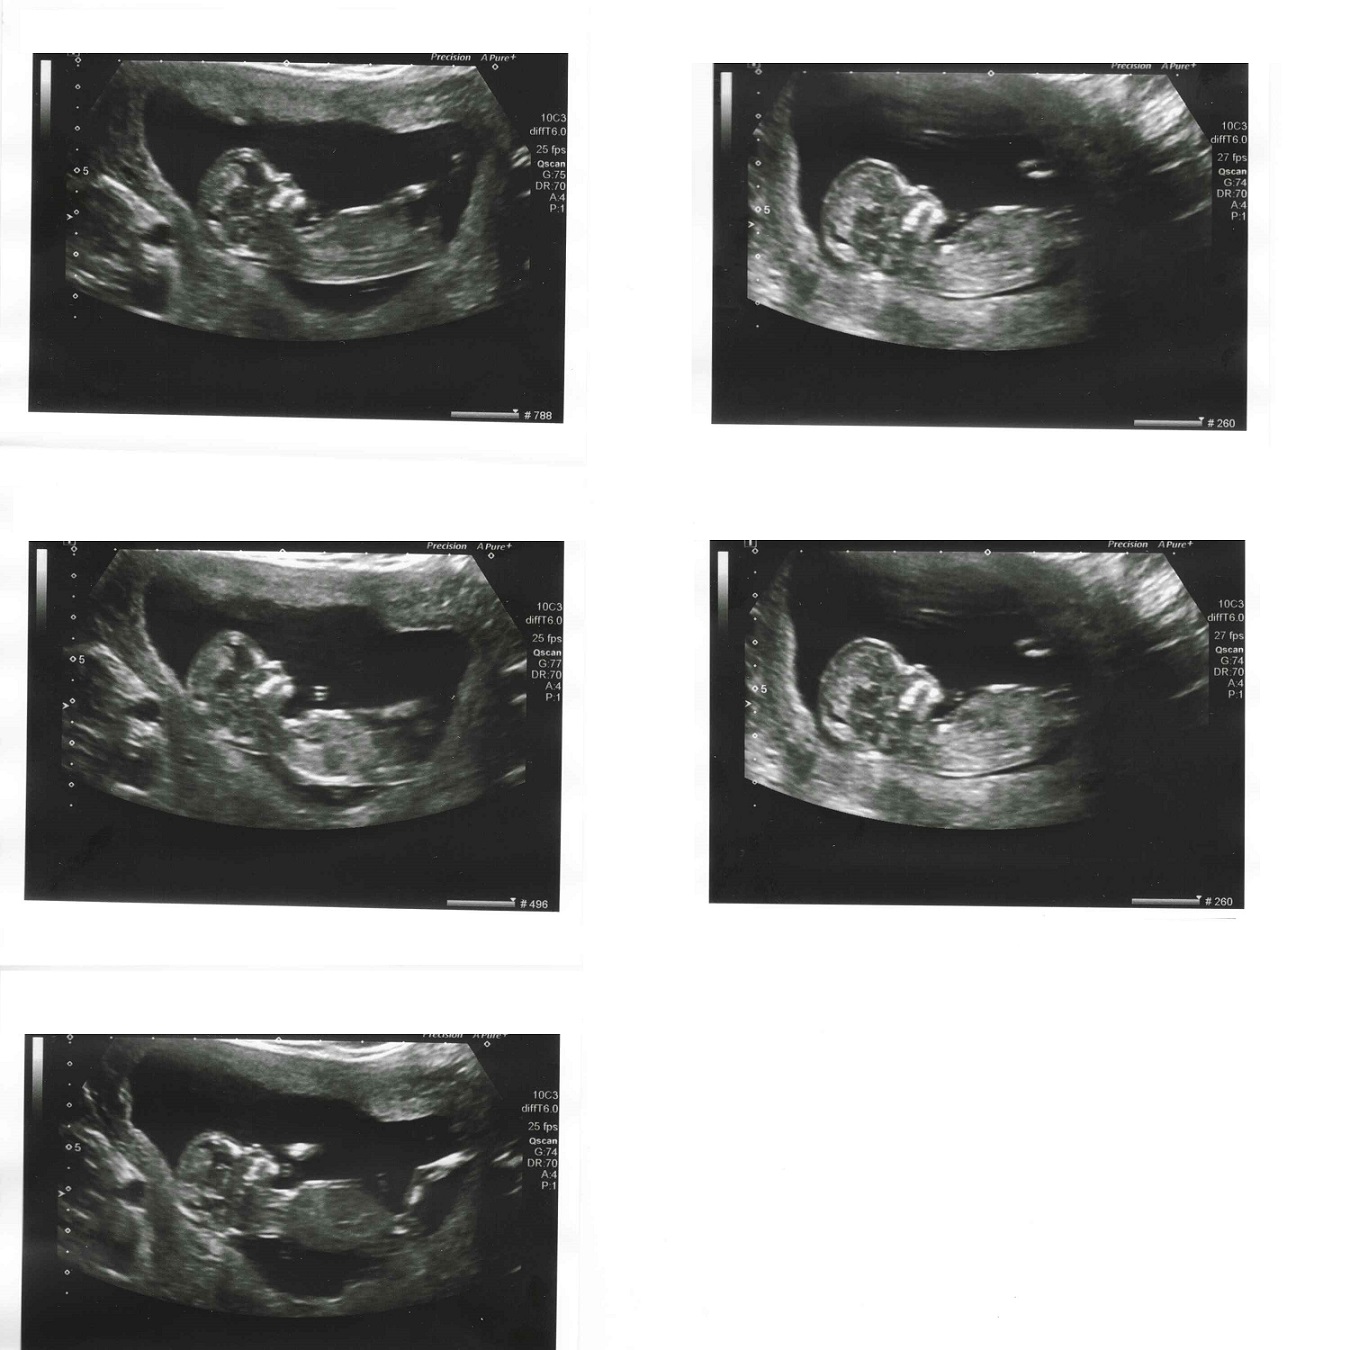

I was hoping some of you guys would have some guesses for me! This is our first baby and I'm 12w2d. Thank you!!

Thinking maybe boy. Congrats!

nub looks like it's on the rise, thinking blue!

boy lean

boy lean based on the second picture down on the right. Thats your best shot with the nub

Maybe boy.

Thanks everyone! I don't see anything in any of the pics, so it's interesting to hear what you guys see. :)